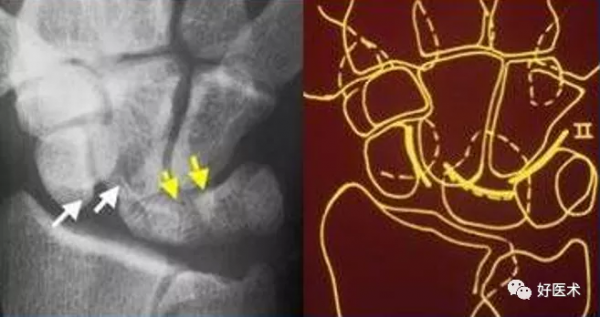

a. M形腕掌線 b. 腕骨弧線(Gilula線)

若顯示腕骨弧線不連續或各弧線不平行,或腕掌線M形結構消失,應高度懷疑腕關節不穩或脫位。

上圖顯示月骨和頭狀骨、鉤骨、三角骨異常重疊,而舟骨與其也不平行,橈月關節間隙異常增寬,其它腕骨間隙平行而勻稱。此為單純月骨脫位。